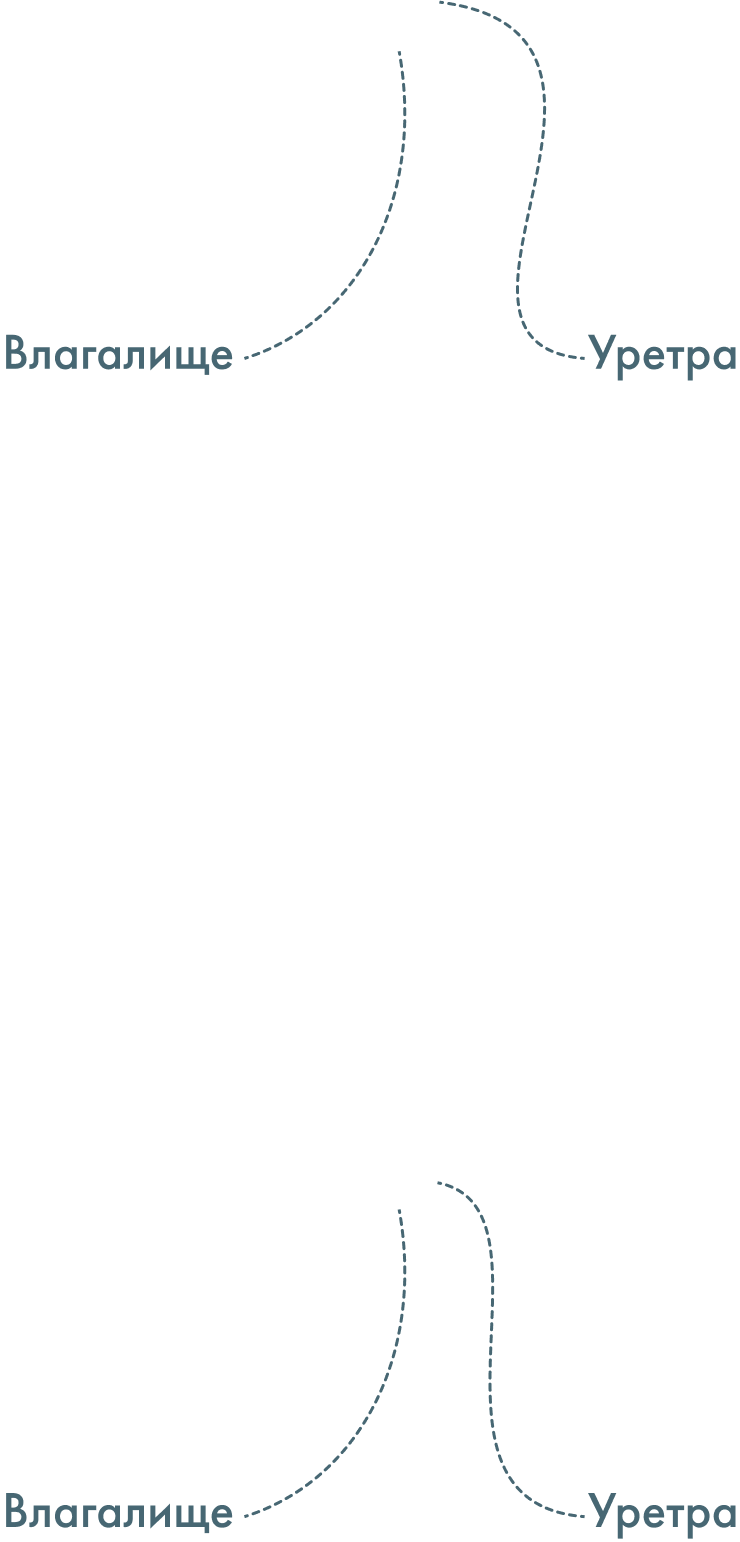

- смещение (эктопия) наружного отверстия уретры к входу во влагалище, а иногда даже на его переднюю стенку. Может сопровождаться недоразвитием и укорочением уретры;

- гипермобильность дистального отдела уретры, в т.ч. из-за формирования гименоуретральных спаек между остатками девственной плевы и наружным отверстием уретры;

Гипоспадия у женщин